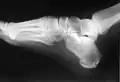

Le calcanéus peut subir des fractures.

Squelette du pied, surface médiale.

Squelette du pied, surface latérale.